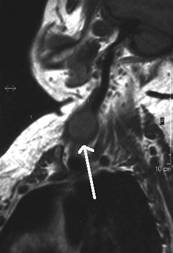

Aceeasi pacienta cu mica formatiune

nodulara medial de carotida dreapta - IRM

Aceeasi pacienta. IRM evidentiaza o formatiune neevidentiata ecografic, metastatica histologic.